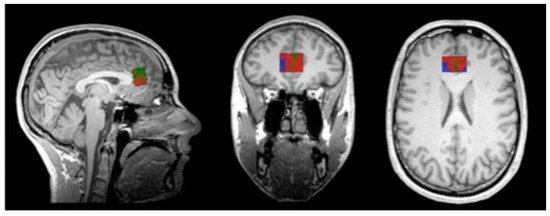

- Rorden, C.; Brett, M. Stereotaxic display of brain lesions. Behav. Neurol. 2000, 12, 191–200. [Google Scholar] [CrossRef] [PubMed]